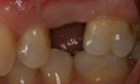

Before and After Pictures

The above images demonstrate the sequence of events for replacing a single missing tooth with a dental implant. The implant fixture is placed and allowed to heal, then a post or abutment is seated, and then a final crown is placed on top.